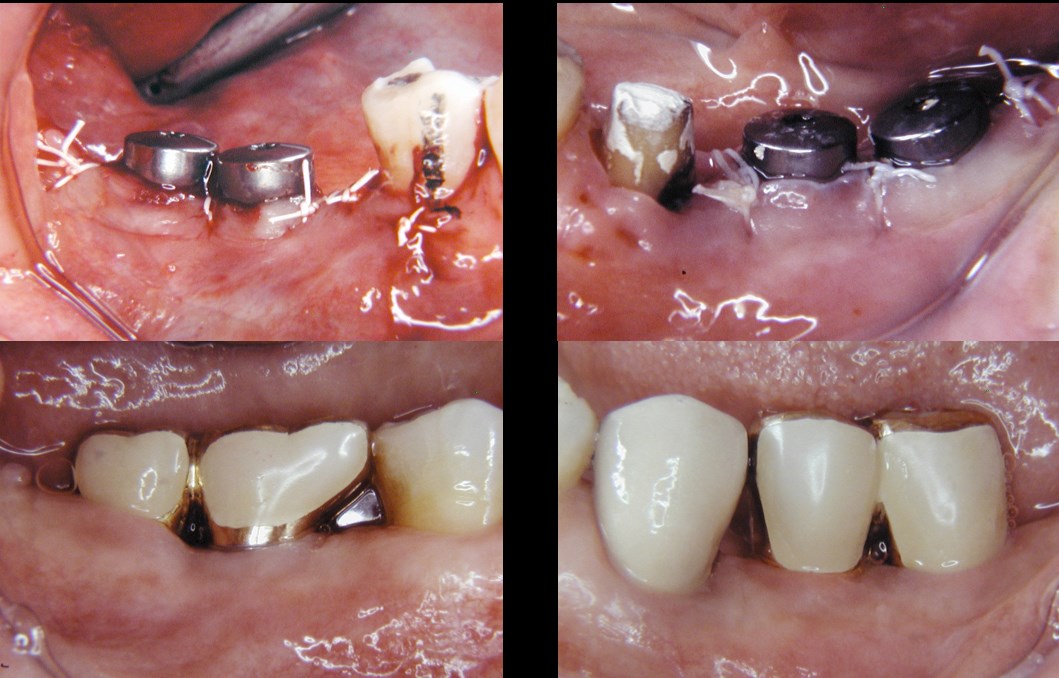

治療の流れ

術後経過